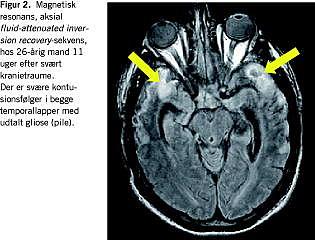

Fluid-attenuated inversion recovery (FLAIR) er en anden værdifuld MR-sekvens, som specielt muliggør visualisering af læsioner nær cerebrospinalvæsken, hvilket ellers er vanskeliggjort af det kraftige signal herfra [3]. Nonhæmoragiske DAI-læsioner kan sommetider synliggøres med denne sekvens. FLAIR er desuden velegnet til visualisering af andre traumatiske læsionstyper eksempelvis kontusioner [3] (Figur 2 ).